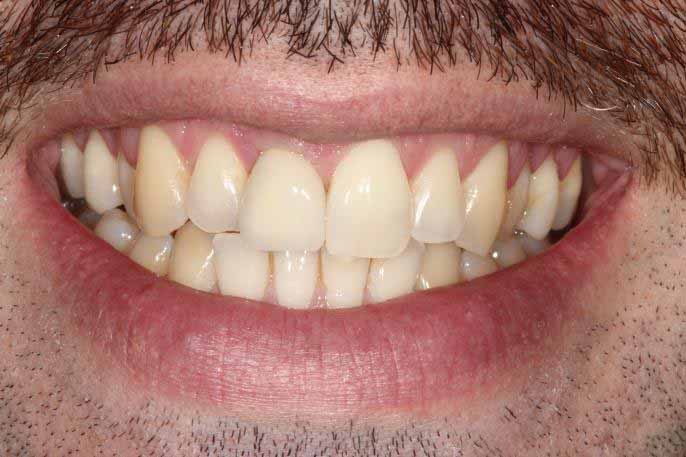

Upper Front Tooth Implant

Both upper front teeth were in a bad way, the upper left one had to be removed as was beyond repair, this was replaced with an implant and a temporary crown on the same day; the upper right front tooth was repaired with a crown. Photos show the result with the definitive crowns after 3 months of treatment.